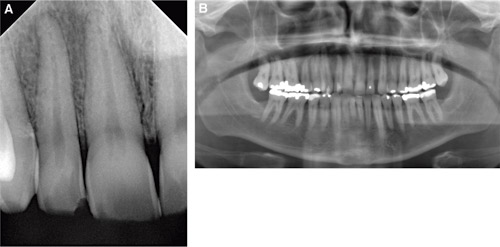

En 51 år gammel mann ble henvist parallelt fra sin tannlege og lege til Kjevekirurgisk poliklinikk, Haukeland universitetssykehus, for utredning av langvarige smerter i overkjevens høyre side. Mannen var frisk uten kjente allergier eller sykdommer. Pasienten tok først kontakt med egen tannlege på grunn av sterk, intens smerte som debuterte fra tann 12. Klinisk var tannen intakt, men sterkt perkusjonsøm. Anamnesen ga ingen indikasjon på traume, og røntgen viste intakt tann uten tegn til patologi (Figur 1A). Tannlegen utredet problemstillingen og konkluderte med sannsynlig akutt pulpitt og påbegynte endodontisk behandling med pulpaekstirpasjon og kalsiumhydroksidinnlegg. Pasienten tok igjen kontakt med sin tannlege etter kort tid pga. økende smerter. Smertene hadde nå spredd seg til nabotannen 13. Endodontisk behandling av 13 ga heller ingen symptomlindring. I løpet av en uke spredte smertene seg til alle tennene i 1. kvadrant, i tillegg til en uttalt palpasjonsømhet i hele 1. kvadrant. Pasienten ble utredet for samme problemstilling hos fastlege og ble også undersøkt av øre-nese-hals-lege uten klare funn.

Figur 1 A og B. Intraoral bilde før endodontisk behandling (A) og OPG- bilde (B) etter oppstart av endodontisk terapi. Bildene viser normale apikale forhold.

Pasienten ble undersøkt ved Kjevekirurgisk poliklinikk en måned etter første tannlegekonsultasjon, etter en ny akutt smerteepisode. Denne gangen strakk smerten seg opp mot kinnet og overleppen på høyre side (Figur 2). Smertene varierte i løpet av dagen og ble intense ved berøring av området. Flere tenner var perkusjonsømme i 1. kvadrant. Det ble ikke påvist tegn til submandibulær lymfadenitt og intraorale røntgenbilder og ortopantogram (OPG) viste ingen patologi med unntak av mulig svak utvidet rothinnespalte på 12 og 13 (Figur 1 B). Det ble startet antibiotikabehandling med fenoksymetylpenicillin (Apocillin®, 660 mg x 4), men uten at dette hadde effekt på symptomene til pasienten. Tennene i 1. kvadrant var fremdeles perkusjonsømme. I tillegg var det uttalt palpasjonsømmhet i omslagsfold i regio 11 til 16, med en hard oppfylling i samme området (Figur 3). Hevelsen var ikke-flukturerende, med rubor og uttalte blodkar i overdekkende slimhinne, men ingen registrert vesikkeldannelse. Det ble registrert mobilitet, grad I til II, på tennene 11 til 15. Sensibilitetstest var negativ på samtlige tenner i første kvadrant (tann 11 til 17). Det ble rekvirert en rekke blodprøver der både hemoglobin (Hb), C-reaktivt protein (CRP), leukocytter og trombocytter lå innenfor referanseverdiene. Fastlege hadde allerede henvist pasienten for computer tomografi (CT)-utredning av ansikt/kjeveområdet som viste normale beinstrukturer uten tegn til infeksjon eller malignitet i maxilla. I mellomtiden hadde pasienten kontinuerlig brukt både ibuprofen (Ibux®600 mg) og Pinex forte® tabletter med kun moderat effekt.